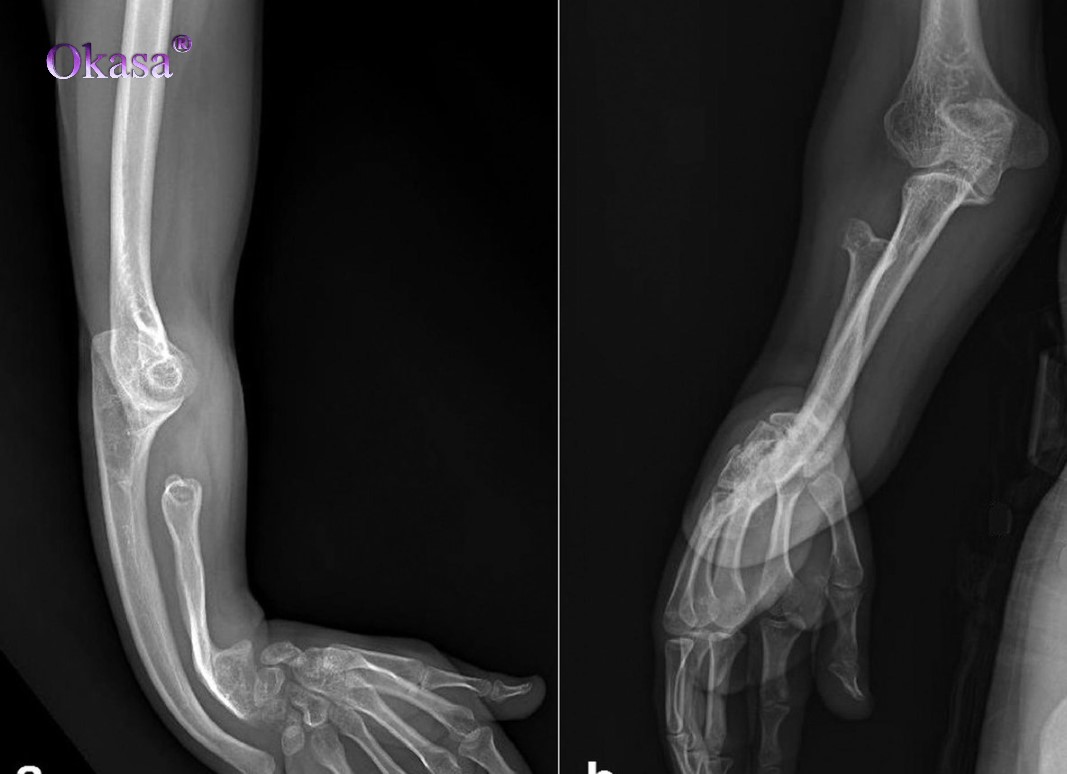

Để biết được tình trạng bệnh, các bác sĩ sẽ tiến hành đo mật độ xương, đây là phương pháp kiểm tra độ loãng xương sẽ chẩn đoán được người bệnh bị thiếu xương hay loãng xương.

Khi đo mật độ xương sẽ biết được mức canxi trong xương, và cũng từ kết quả đó để chẩn đoán, đánh giá nguy cơ gãy xương của bệnh nhân.

Đo độ loãng xương là phương pháp kiểm tra được thực hiện ở xương hông, cột sống, cổ tay, ngón tay hoặc gót chân…đây là phương phápkhông xâm nhập và không gây đau đớn cho người bệnh.